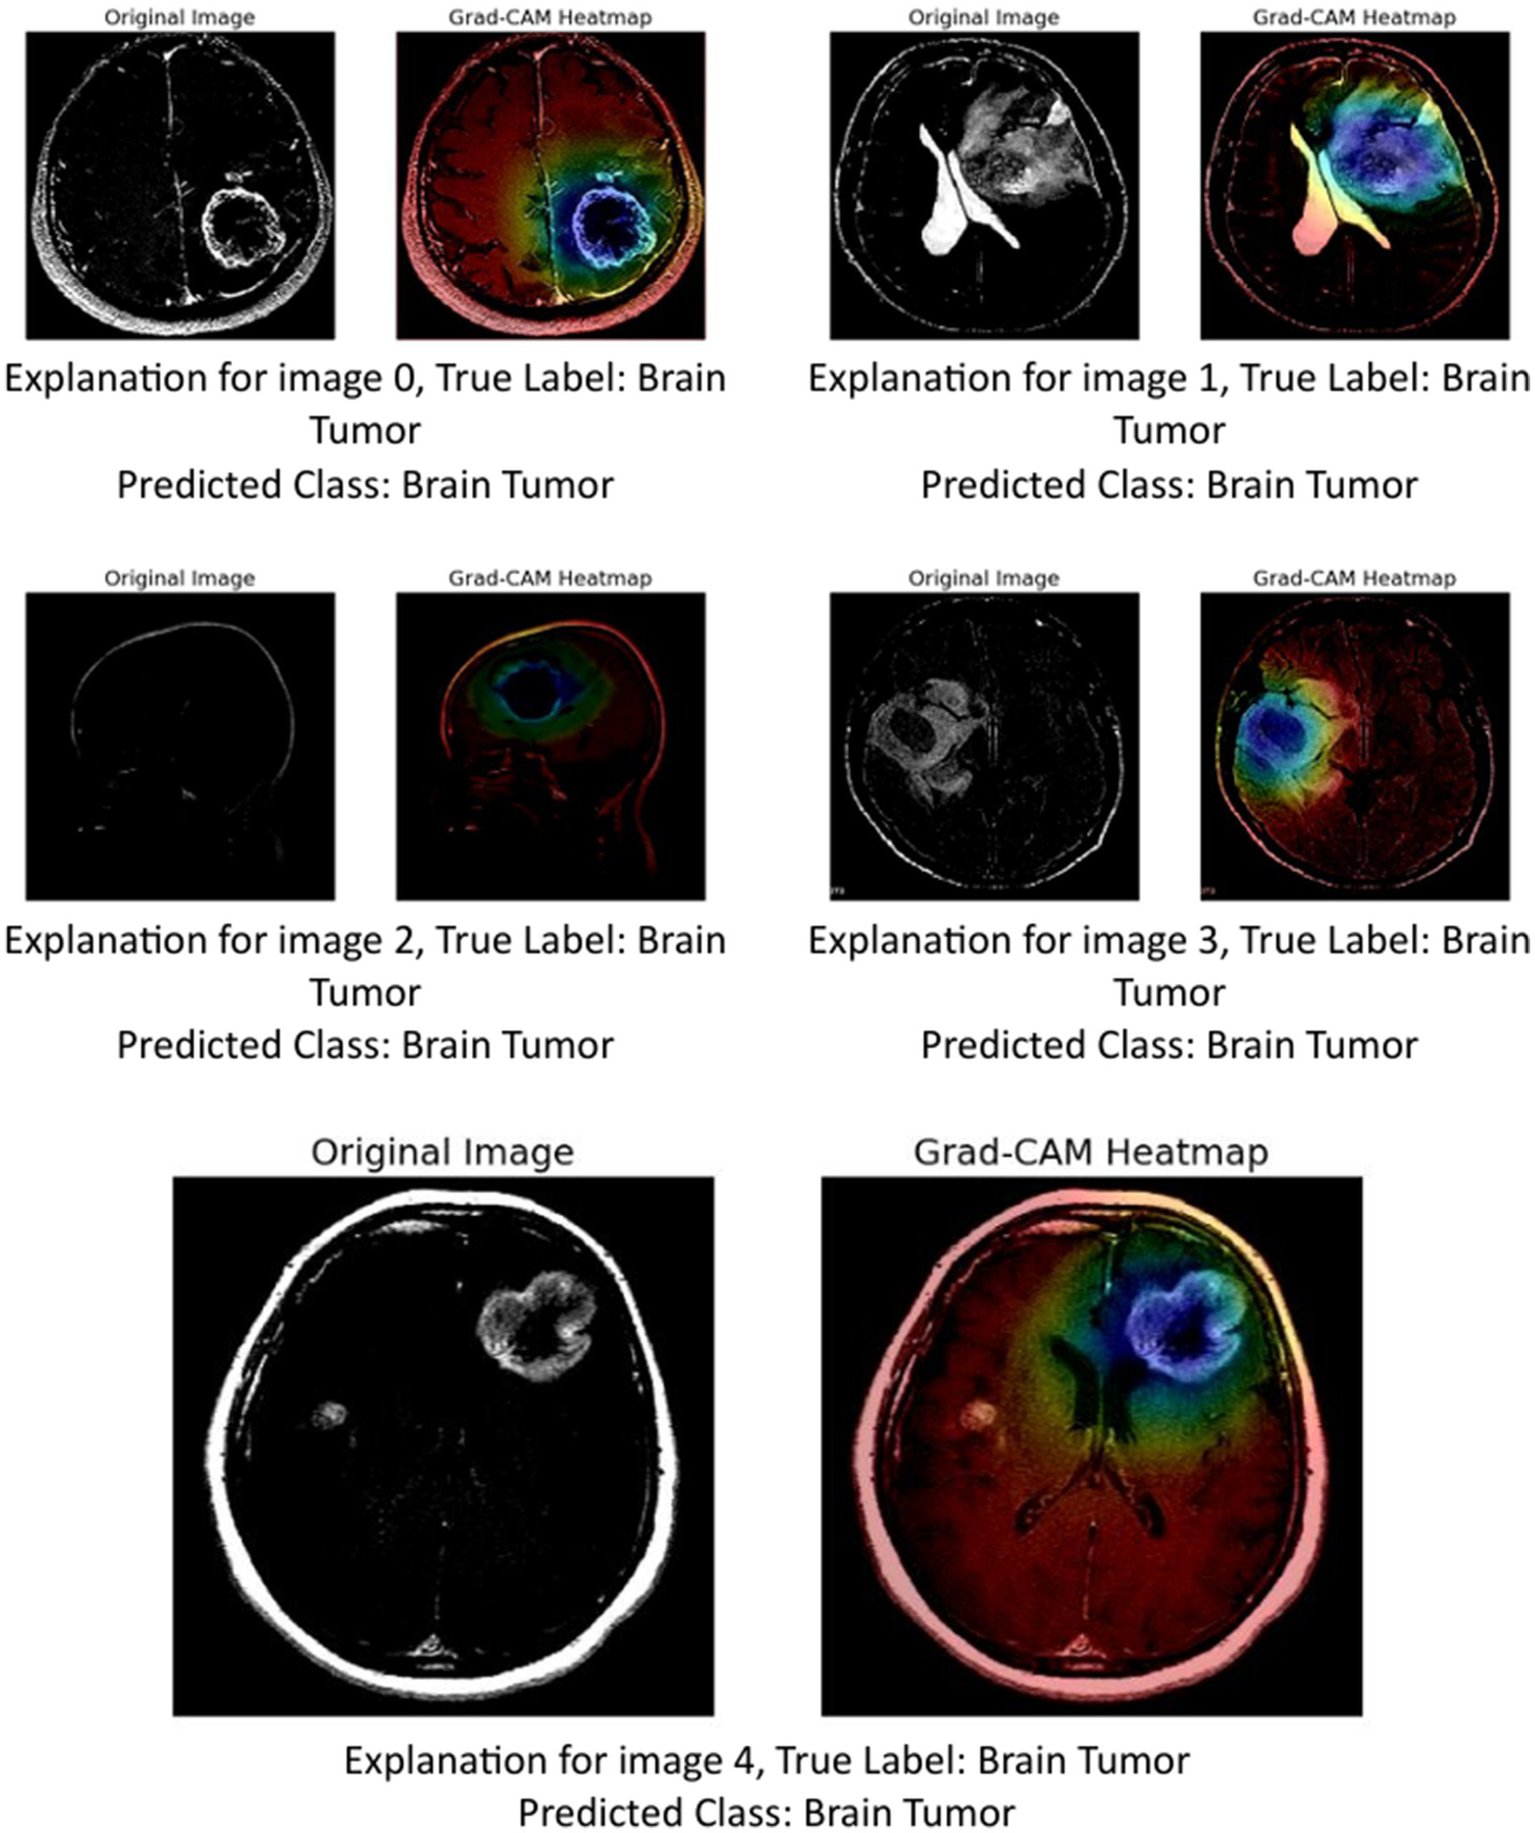

The image above presents Grad-CAM (Gradient-weighted Class Activation Mapping) visualizations applied to five MRI brain scan samples, all of which are correctly classified as showing a Brain Tumor. Grad-CAM is a powerful interpretability technique that helps understand which parts of the input image contribute most to a neural network’s decision, particularly in convolutional neural networks (CNNs) (Mir and Pal, 2025; Tsai and Lee, 2025).

In the Grad-CAM heatmaps:

-

The red to yellow regions represent high model attention or importance—areas that had a strong influence on the model’s decision to classify the scan as showing a brain tumor.

The blue to green regions represent areas of lesser importance.

The heatmap is superimposed on the original image to show where the model “looked” most carefully.

Let us break down the explanation per image:

Image 0: The tumor is visible in the lower right area of the brain scan. The Grad-CAM heatmap highlights this same region in red, confirming that the model’s prediction is based on the actual tumor site.

Image 1: The tumor appears slightly more complex and irregular in structure. The heat-map shows attention on the central part of the brain, especially around the bright white tumor region, suggesting the model used this area to identify the abnormality.

Image 2: This scan is a side profile (sagittal view), making interpretation more complex. Despite the different orientation, the Grad-CAM heatmap still highlights the central mass with strong attention, indicating that the model adapted well and localized the tumor area accurately.

Image 3: The tumor appears to occupy a deeper region of the brain. The model again focuses on this region, with the heatmap showing a dense red spot right on the tumor, reinforcing the reliability of the model’s detection.

Image 4: The tumor here is located in the upper right quadrant of the scan. The heatmap aligns with this mass, highlighting it in red and confirming that the model’s prediction was influenced by the actual tumor.

These Grad-CAM visualizations demonstrate (Figure 12) that the model consistently focuses on the correct anatomical regions associated with brain tumors. The heatmaps provide visual confirmation that the CNN is not relying on irrelevant or misleading features, but rather, is making predictions based on medically significant areas. This enhances the interpretability and trustworthiness of the AI model in a sensitive application like medical diagnostics, where understanding the reasoning behind a decision is crucial for clinical validation.

Figure 12

GRAD-CAM visualization.